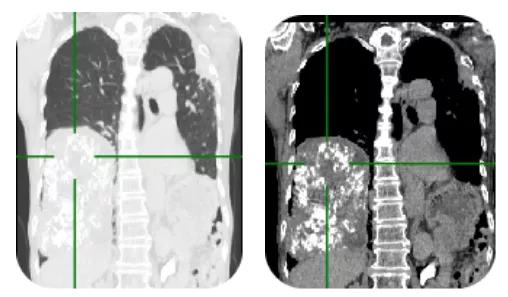

79岁的殷老太近半月来出现胸闷乏力,CT检查发现:老人右侧胸腔有一个约15cmx14cmx10cm的巨大肿瘤,将心脏、左肺和纵隔的大血管结构挤压移位。经济宁市第一人民医院胸外科张康主任团队努力,为其进行全麻双腔气管插管下右肺肿瘤及右肺下叶切除加纵隔淋巴结清除术,历时1个半小时,成功为老人摘除右肺巨大肿瘤。

入院后,张康专家团队对老人病情进行全面的检查和评估。检查发现右侧胸腔有一个巨大的肿瘤,压迫左肺、心脏、膈肌、右肺;肿瘤与膈肌、右肺动脉等胸腔内的大血管关系密切。结合患者病情,手术切除病变是目前最有效的治疗方案。

面对复杂的疾病,张康主任仔细研究了患者胸部CT三维重建,明确了右肺肿物的解剖血供情况,评估了手术风险。最终,向殷老太太的儿女交代了手术的必要性,患者因右肺巨大肿瘤压迫右肺、左肺及膈肌、心脏,同时既往左肺下叶已被切除,肺功能损失严重,并且年龄大、体质差,导致目前胸闷乏力,严重影响患者日常活动。随着时间的延长,肿瘤会继续生长增大,患者呼吸困难症状将逐渐加重并危及生命。在征得家属同意与理解后,张康主任第一时间为患者安排了手术。

(资料图片)